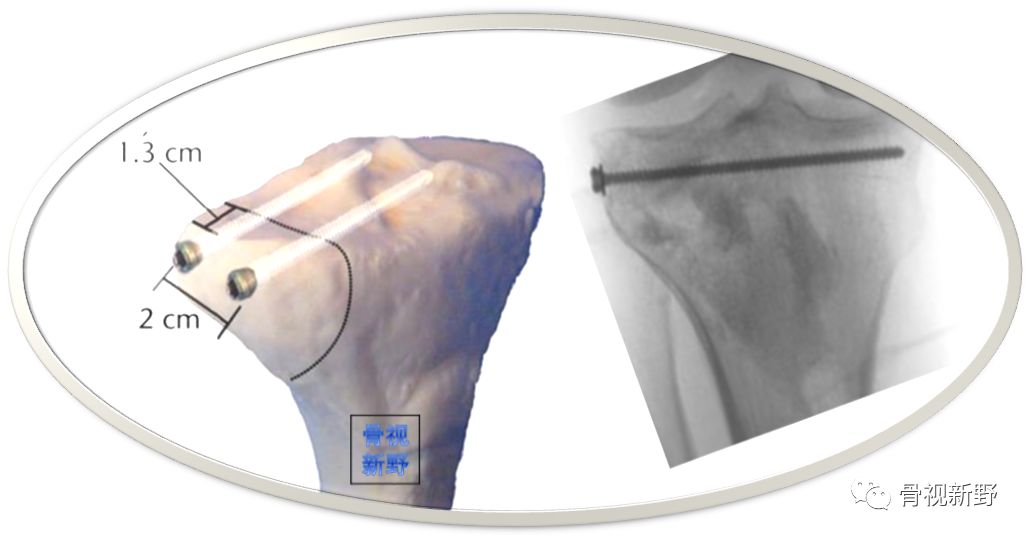

Moran E(2017)对传统“三角螺钉固定”技术进行改良,将第3枚防滑螺钉的方向朝向拉力螺钉的尖端而形成螺钉尖端汇聚,螺钉分布在侧位呈倒“品”字形进钉;正位X光片(或透视)像上螺钉呈三角形分布(如下图)。

具体固定方法:2枚带垫片、相互平行的6.5 mm半螺纹拉力螺钉(相距15 mm)垂直骨折线在距关节面7mm以下打入软骨下骨。第3枚三角固定螺钉选择带垫片的全螺纹6.5mm 松质骨螺钉,从骨折块尖端呈30°角(正位透视)打入,螺钉尖部与2枚拉力螺钉尖部汇合,第3枚螺钉起防滑、支持作用( Moran E 2017)。